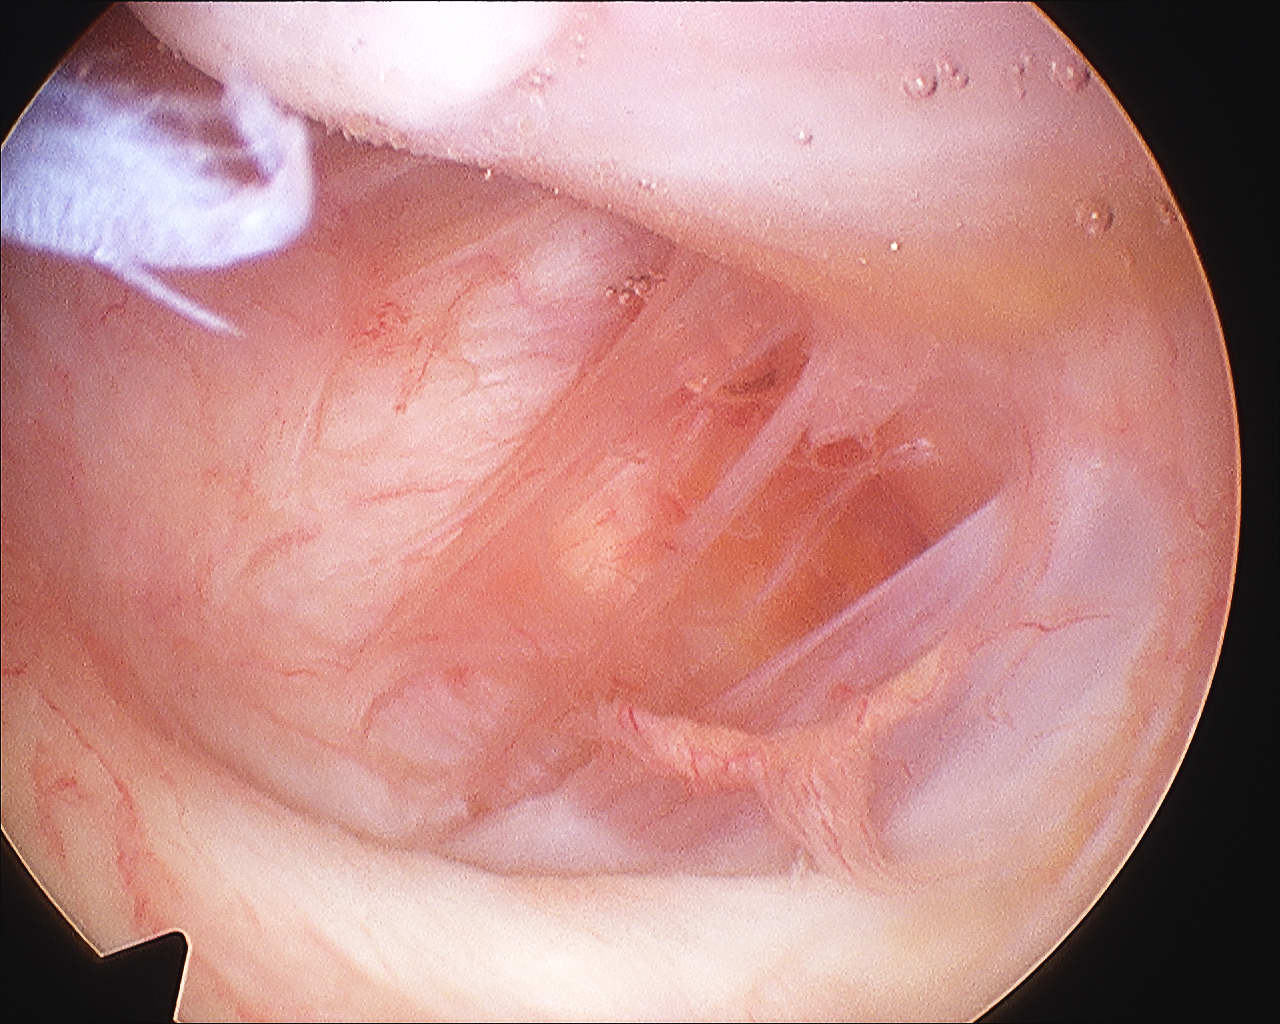

Arthroscopy

Anterior capsule tears

Normal humeral insertion on right, HAGL on left with tearing of IGHL insertion onto humeral neck